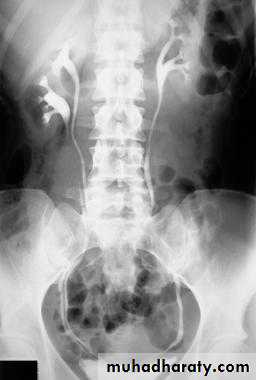

Failure of contrast to pass to ureters due to both sided mid ureteric stones

LT sided upper Ureteric stones

Bilateral HU + HN